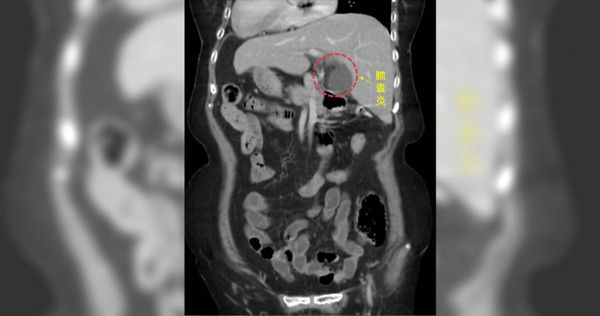

▲正常人的左上腹是胃或大腸,但阿嬤卻是膽囊,醫師透過電腦斷層檢查才發現。(圖/中醫大新竹附設醫院提供)

一位80歲左右的阿嬤,因左上腹痛來中國醫藥大學新竹附設醫院急診,左上腹痛一般應是胃痛或大腸發炎,做了電腦斷層發現阿嬤是一個「鏡面人」,所謂「鏡面人」就是他的內臟等器官跟一般人的位置顛倒,經過一般外科古君平醫師診斷,阿嬤是急性膽囊炎。「鏡面人」左右顛倒的內臟是外科手術挑戰,古君平醫師首次遇到,一般膽囊手術需約半小時即可完成,這次手術花了一個半小時才完成,透過腹腔鏡微創手術,順利切除膽囊,術後兩天就順利出院。

古君平醫師表示,所謂的「鏡面人」包括腹腔、胸腔內器官的位置與一般人剛好相反,例如一般人心臟脾臟在左邊,肝臟位於右邊,鏡面人心臟脾臟在右邊,肝臟在左邊,就好像正常人的鏡中影像,故出現「鏡面人」的稱呼。這是一個罕見的遺傳病,發生率大約是萬分之一左右,不過內臟功能跟一般沒什麼差別,所以只要沒有生病沒做檢查,一般人不會知道自己的內臟跟別人的位置不一樣,這次阿嬤因為急性腹痛做電腦斷層,才發現他的內臟跟一般人相反。